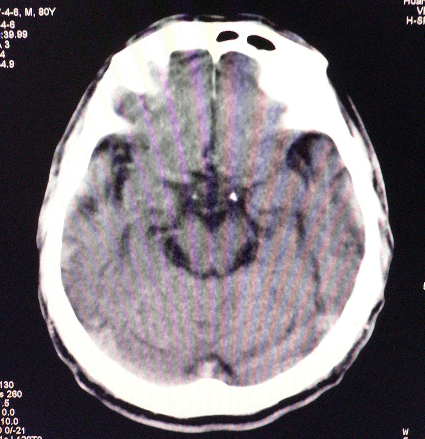

以下是引用狙击手在2007-4-8 22:45:00的发言:[br]出血?从患者的症状考虑病灶应该在左侧大脑半球的基底节区或颞顶部,如此小的病灶引起上述症状的可能性不大,患者可能有梗塞(时间短,目前ct还看不见)或是tia发作,再者像这样的线条形出血的确不多见,但还是有可能的,曾经碰到有外伤类似出血,复查后消失,所以还是慎重一点,短期复查即可。

以下是引用dyqct在2007-4-8 16:25:00的发言:[br]支持左侧放射冠区少量出血。